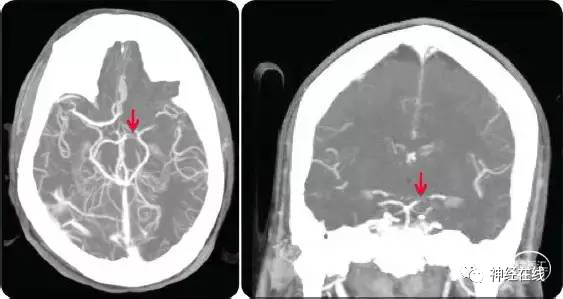

三)影像学检查:CT高密度征阴性;症状-时间-影像不匹配;血栓负荷,侧枝代偿

1. CT高密度征